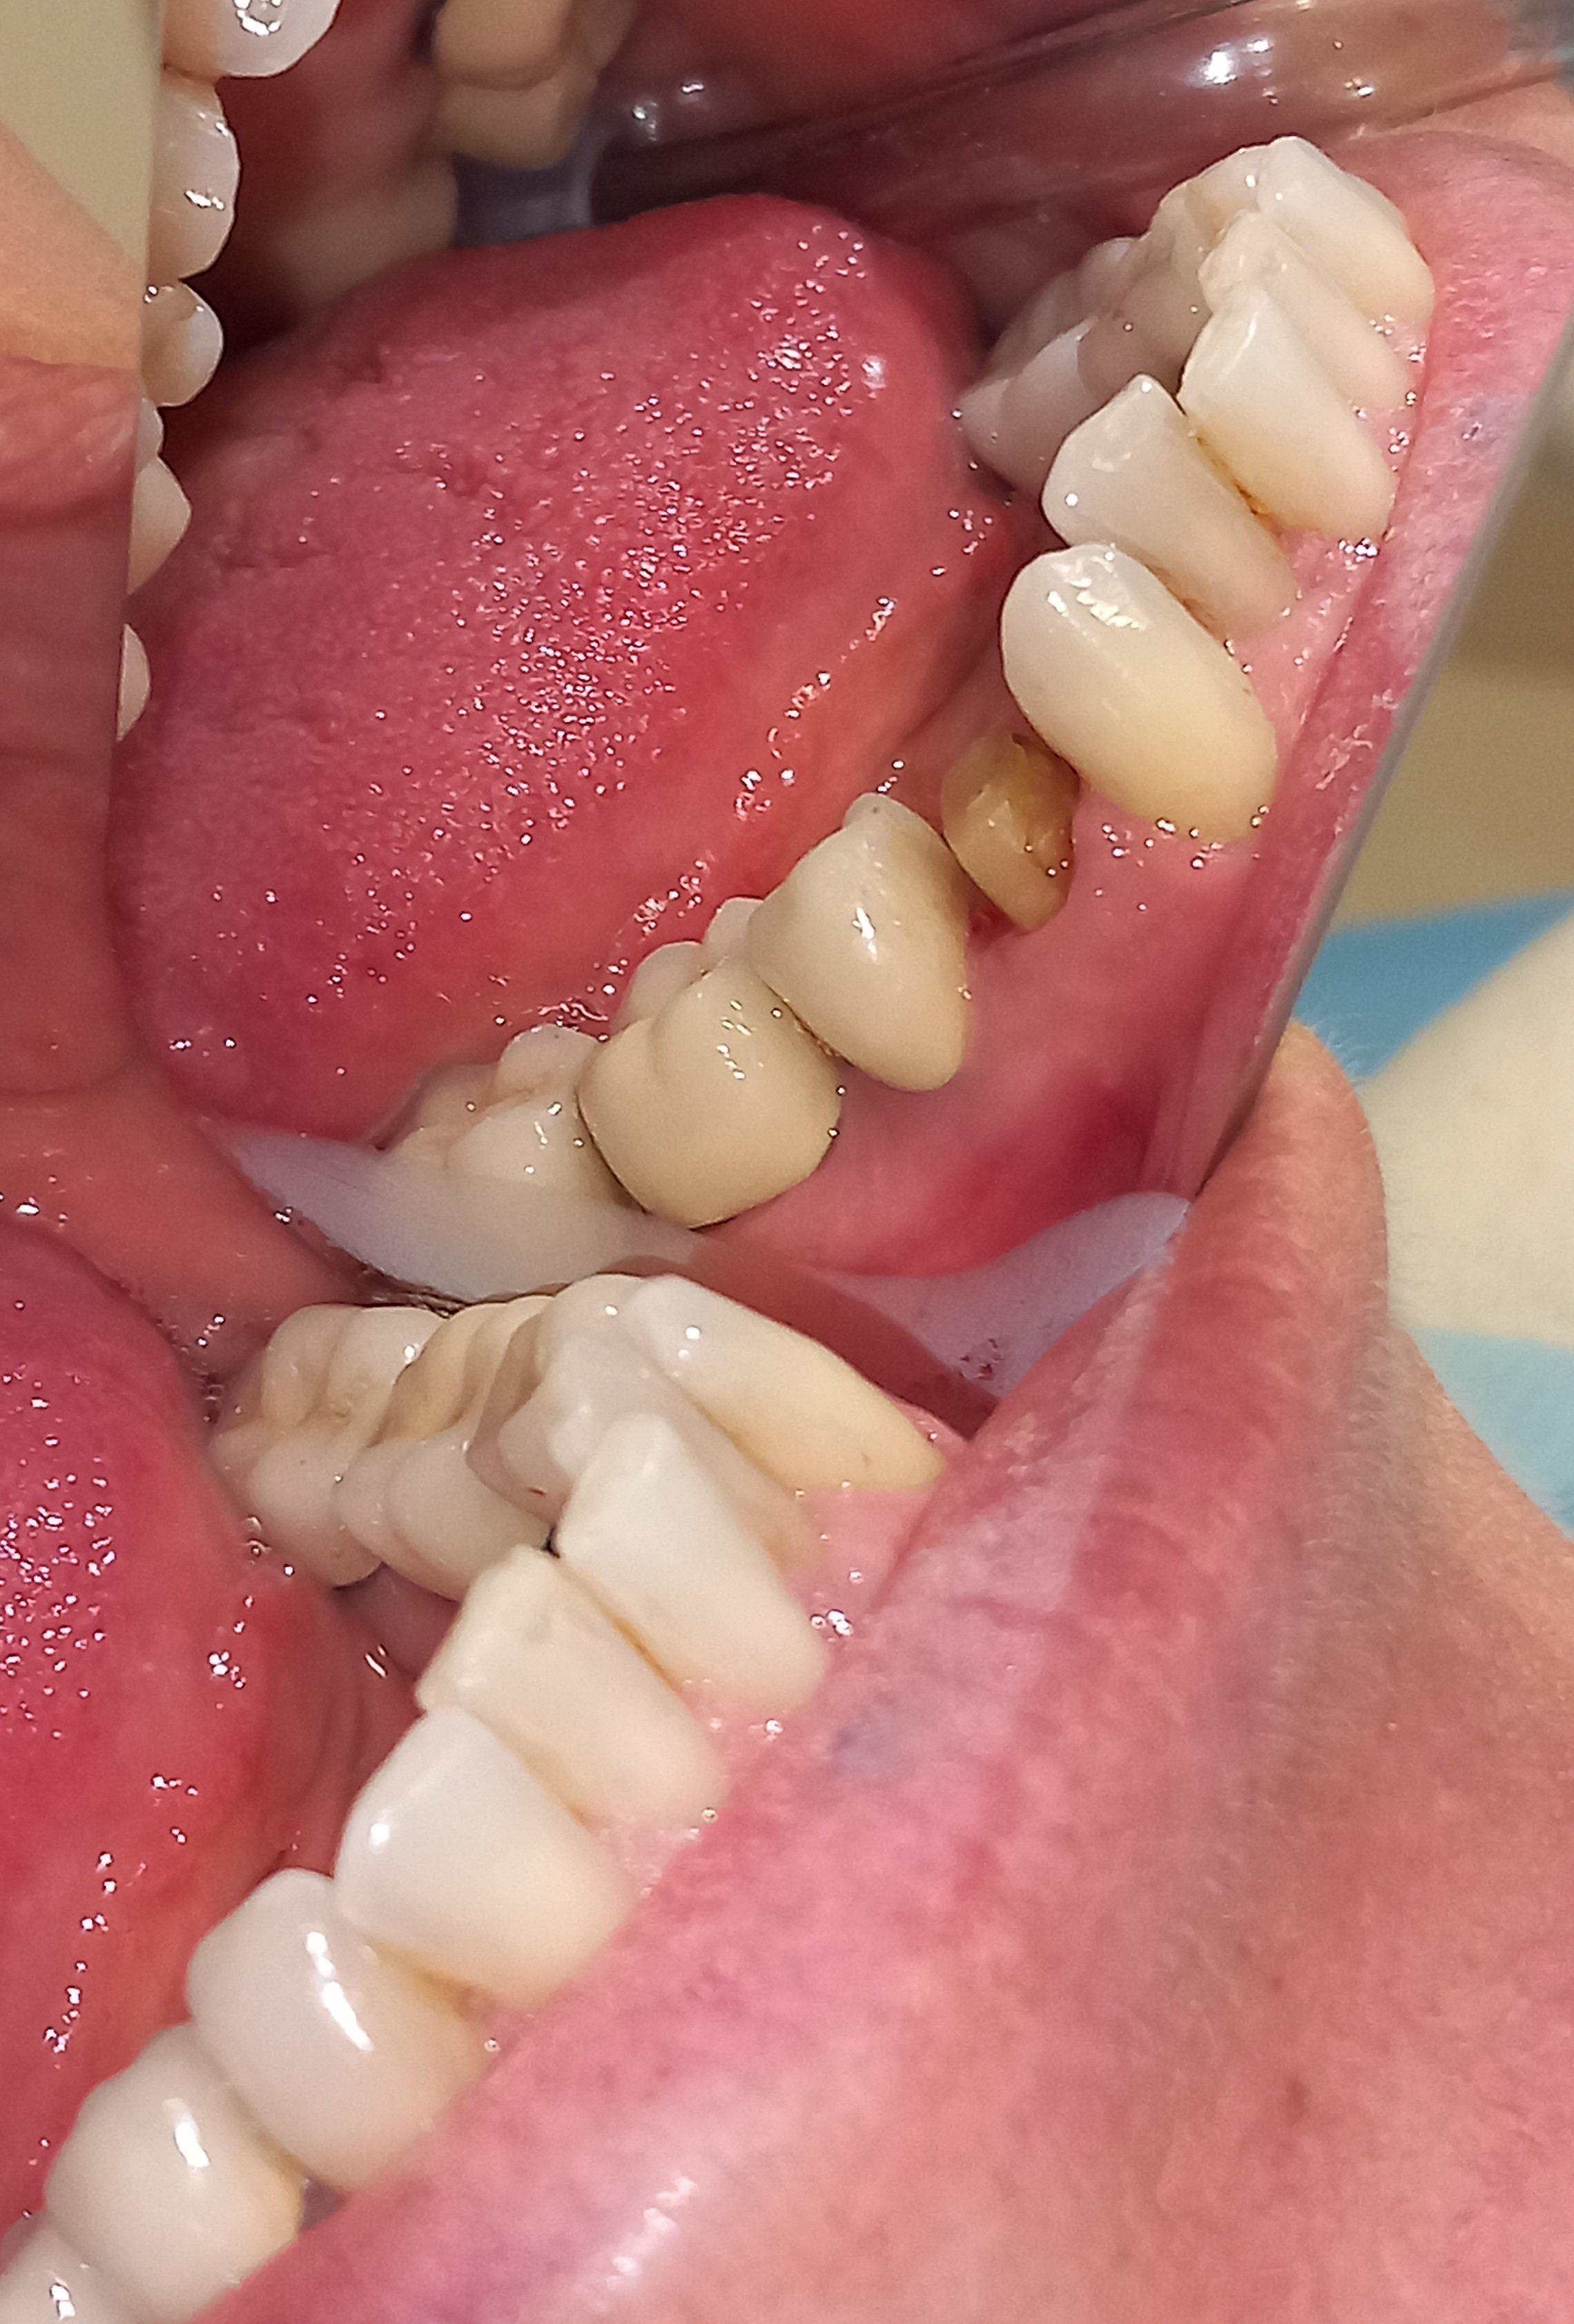

Αρχική εικόνα των δοντιών μετά την αφαίρεση της παλιάς γέφυρας

Τα δόντια μετά τις απαραίτητες απονευρώσεις και τις ανασυστάσεις